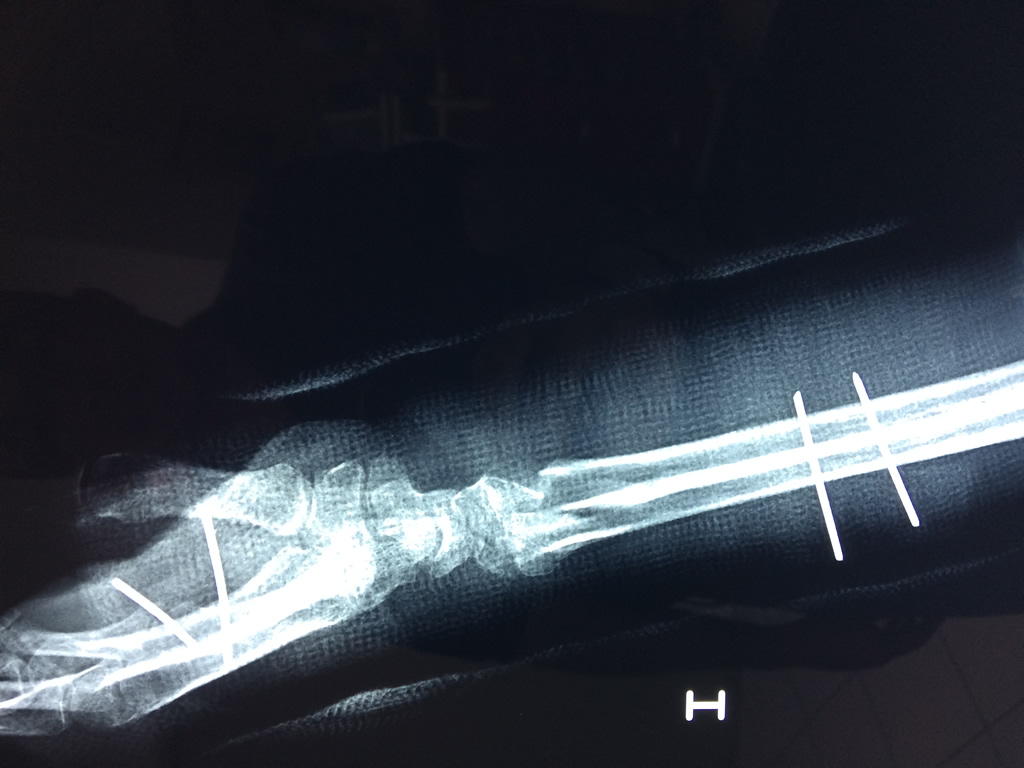

Cirugía de Fémur - Cirugías de Muñecas y Manos

Los procedimientos más comunes en cirugía de la mano son aquellos destinados a reparar traumatismos, incluyendo lesiones de tendones, nervios, vasos sanguíneos, y articulaciones; huesos fracturados; y quemaduras, cortes, y otros daños de la piel.